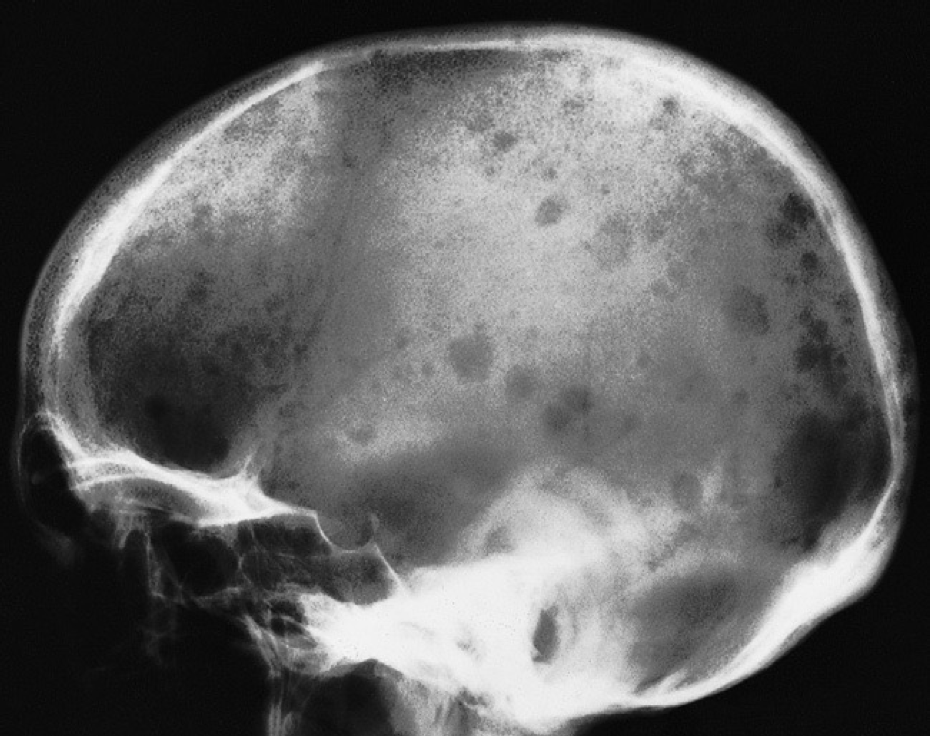

Multiple well-defined lytic lesions of various sizes are seen in all areas of the skull vault.